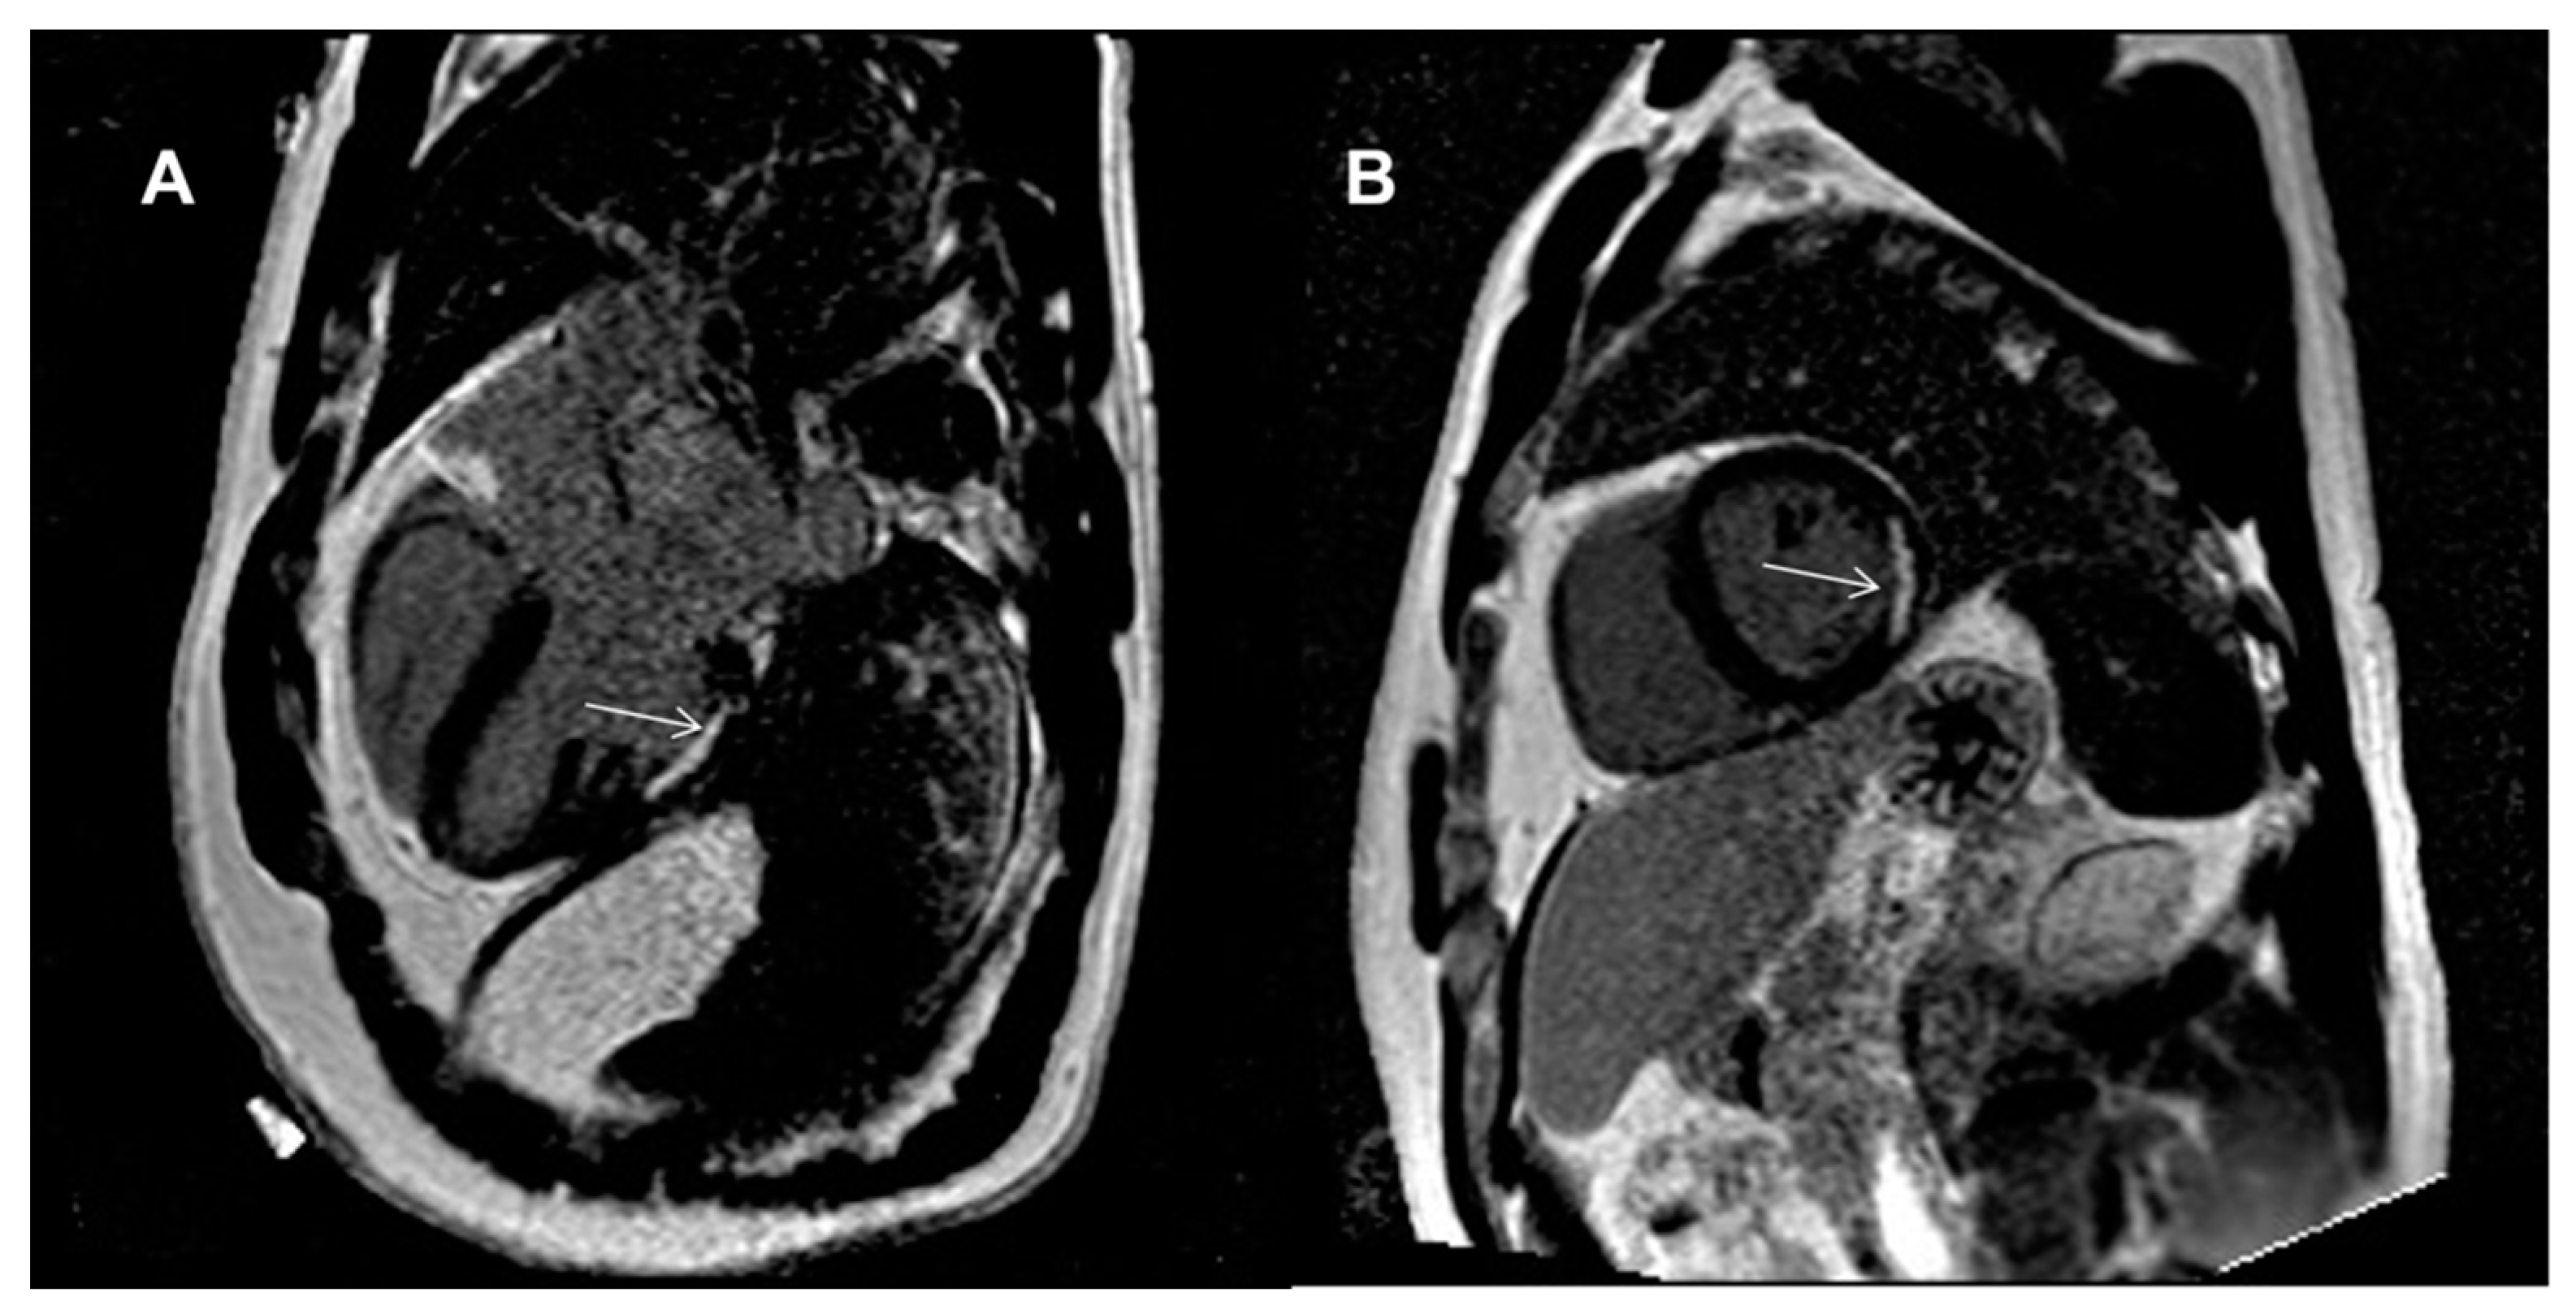

| LGE, n (%) | - | ||

| − subendocardial | 1 (6) | 0 (0) | |

| − mid-wall | 0 (0) | 0 (0) | |

| − subepicardial | 0 (0) | 0 (0) | |